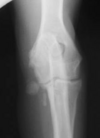

Which radiographs show an active vs. inactive pattern of periosteal reaction?

Left 2 radiographs: inactive; smooth, well defined margins

Right 2 radiographs: active; fuzzy, less sharp margins